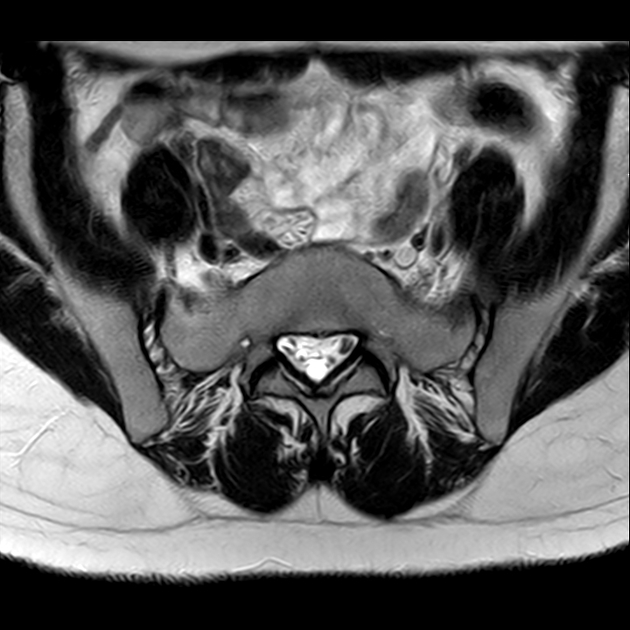

磁共振检查:

T2

6、磁共振上可以发现骨折线周边明显的骨髓水肿,增强扫描明显强化

磁共振影像表现